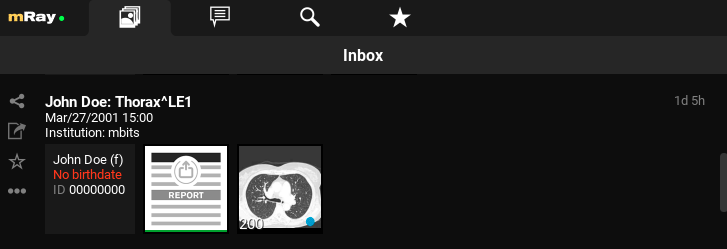

9.1. Inbox

Nach dem Einloggen öffnet sich die „Inbox“ (Inbox). Über diese können Sie den gewünschten DICOM Datensatz selektieren, der Ihnen über den eingestellten Server zur Verfügung gestellt wurde. Sie sehen hier also alle am mRay-Server vorliegenden Daten, auf die Sie Zugriffsrechte haben.

Hier werden Informationen bzw. auch fehlende Informationen und Metadaten zum Patient angezeigt.

-

Hier sehen Sie eine Übersicht der Serien innerhalb der Studie. Durch Anklicken einer Studie kommen Sie in die Serienauswahl (siehe Serienauswahl). Der grüne Balken unter jedem Vorschaubild zeigt an ob der Datensatz lokal auf Ihr Gerät heruntergeladen und offline verfügbar ist.

-

Hier erscheint, wann der Datensatz in der Inbox ankam (d. h. durch Schicken aus dem PACS bzw. Suche im Datenbestand). mRay kann so konfiguriert werden, dass Datensätze automatisch nach 'X' Stunden wieder vom Gerät gelöscht werden (Standard: Nach 8 Stunden).